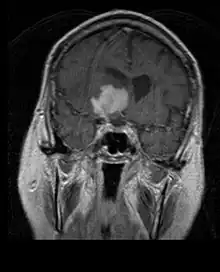

La tomodensitométrie (TDM) et L'imagerie par résonance magnétique (IRM) peuvent détecter efficacement une néoplasie dans le cerveau. L'IRM est plus sensible que la TDM pour identifier les lésions, mais présente des contre- indications pour les patients porteurs de stimulateurs cardiaques, de prothèses incompatibles, de clips métalliques et contre-indications. La TDM reste la méthode de choix pour détecter les calcifications au sein des lésions ou les érosions osseuses de la calotte ou de base du crâne. L'utilisation d' agents de contraste, iodés dans le cas du scanner et paramagnétiques (gadolinium) dans le cas de l'IRM, permet l'acquisition d'informations sur la vascularisation et l'intégrité de la barrière hémato-encéphalique, une meilleure définition de la tumeur tumorale par rapport à l' œdème environnant et à la génération d' hypothèses sur le degré de malignité. L'examen radiologique permet également d'évaluer les effets mécaniques et les modifications importantes des structures cérébrales résultant de la tumeur, telles que l' hydrocéphalie et les hernies, dont les effets peuvent être fatals. Enfin, en préparation à la chirurgie, ce diagnostic peut être utilisé pour déterminer la localisation de la lésion ou l'infiltration de la tumeur dans des zones vitales du cerveau. À cette fin, l'IRM est plus efficace que la tomodensitométrie car elle peut fournir des images en trois dimensions.

Sur-L'IRM montre une tumeur intracrânienne comme une lésion massive qui peut devenir plus luminescente après utilisation du produit de contraste. Cependant, il y a toujours une anomalie de signal dans -L'imagerie par résonance magnétique, qui indique la présence d'une néoplasie ou d'un œdème vasogénique. Habituellement, une luminescence accrue (amélioration du contraste) indique une tumeur d'un grade supérieur de malignité. Un anneau de contraste est caractéristique du glioblastome, avec la partie luminescente correspondant à la partie vitale de la tumeur maligne, et la plus foncée - zone hypointense correspondant à une nécrose tissulaire.

Les patients souffrent d'une variété de symptômes caractéristiques d'une lésion massive focale ou multifocale. L'IRM montre généralement des tumeurs avec un rehaussement de contraste homogène au sein de la substance blanche périventriculaire profonde. La multifocalité et le rehaussement inhomogène sont typiques des patients dont le système immunitaire est affaibli. L'analyse du lymphome du SNC est extrêmement importante dans le diagnostic différentiel de la néoplasie cérébrale. Il est à noter que l'administration de corticoïdes peut entraîner la disparition complète du rehaussement, rendant difficile le diagnostic des lésions. Par conséquent, si un lymphome du SNC doit être pris en compte dans le diagnostic différentiel, les corticoïdes doivent être évités à moins que l'effet de masse ne provoque un problème grave et immédiat chez le patient.

Les métastases cérébrales sont les néoplasmes intracrâniens les plus courants chez les adultes, étant dix fois plus fréquents que les tumeurs cérébrales primaires. Ils marchent à 20 jusqu'à 40 pour cent des adultes atteints de cancer et sont principalement associés au cancer du poumon et du sein et au mélanome . Ces lésions résultent de la propagation des cellules cancéreuses dans la circulation sanguine et surviennent le plus souvent à la jonction de la matière grise et blanche, où la section transversale des vaisseaux sanguins change, emprisonnant les embolies de cellules tumorales . 80 % des lésions surviennent dans les hémisphères cérébraux, 15 pour cent dans le cervelet et 5 pour cent dans le tronc cérébral. Environ 80 % des patients ont des antécédents de cancer systémique et 70 pour cent ont de multiples métastases cérébrales.

Des progrès significatifs ont récemment été réalisés dans le diagnostic et le traitement de ces lésions, entraînant une amélioration de la survie et du contrôle des symptômes. L'apparition des signes et des symptômes est similaire à celle d'autres lésions massives du cerveau. La méthode de diagnostic de choix est l'imagerie par résonance magnétique utilisant des produits de contraste.